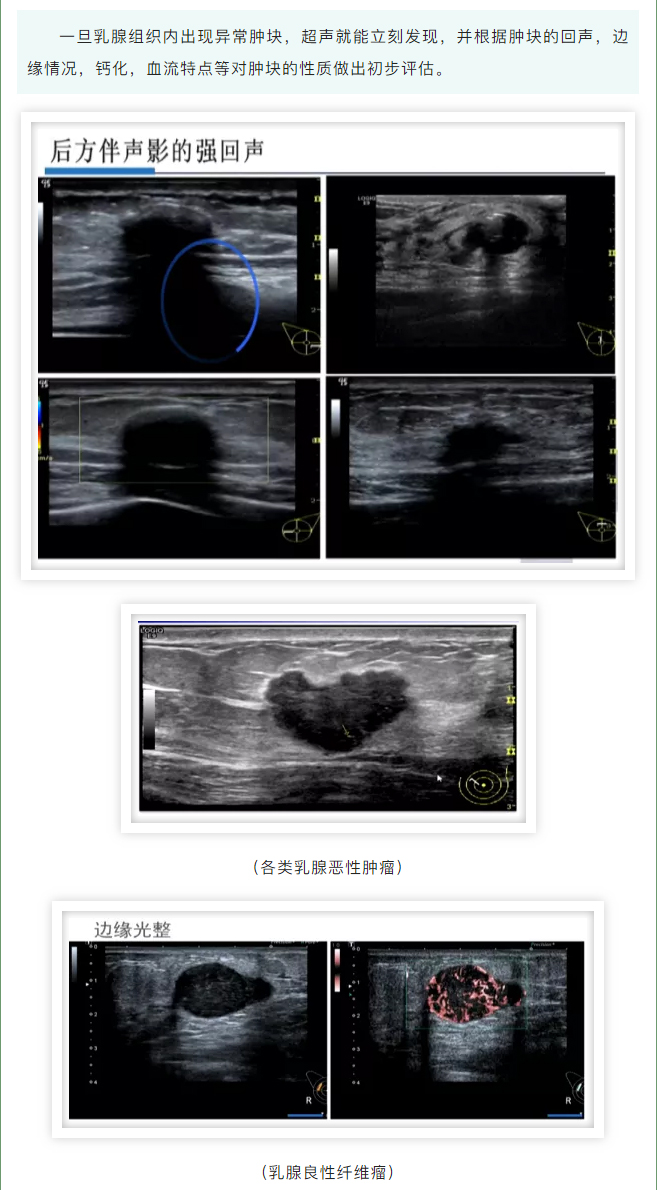

发现乳腺肿块,它俩帮了大忙!_03.jpg

发现乳腺肿块,它俩帮了大忙!_04.jpg

发现乳腺肿块,它俩帮了大忙!_05.jpg